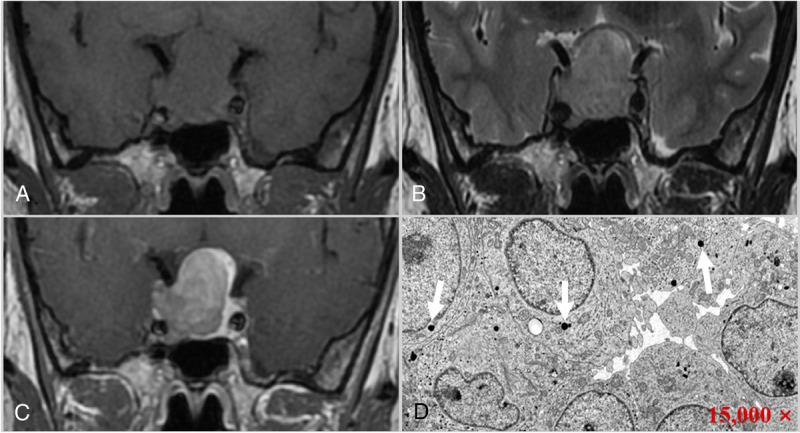

The clinical and MR imaging data of 70 patients with growth hormone pituitary adenoma confirmed by surgery and pathology were retrospectively analyzed. The tumors were divided into dense granular (DG; 36 cases) and sparse granular subtypes (SG; 34 cases). The tumors' MR features were analyzed, including the mean and maximum diameters, T2 signal intensity, T2 relative signal intensity (rSI), homogeneity, enhancement degree, and invasiveness (Knosp grade). Mann-Whitney U test and χ2 test were used to analyze MR characteristics between the 2 groups. The independent predictors and predictive probabilities of tumor subtypes were obtained via a logistic regression model, and the efficacy was compared by receiver operating characteristic curve.

RESULTS

The mean and maximum diameters of growth hormone adenoma in DG and SG were 1.77 versus 2.45 and 1.95 versus 3.00 cm (median, P < 0.05), respectively. There was a significant difference between the 2 groups in T2 signal intensity and rSI (P values were 0.02 and 0.001, respectively). Most DG adenomas (86.1%) appeared as hypointense on T2 images, and 38.2% of SG adenomas were hyperintense. There was no significant difference in tumor homogeneity (P = 0.622). A significant difference was found in the Knosp grade between the 2 subtypes (P = 0.004). In addition, the enhancement degree of SG adenomas was significantly higher than that of DG adenomas (P = 0.001). Logistic regression analysis showed that high T2 rSI value and marked contrast enhancement were independent predictors of the 2 subtypes, and the odds ratios were 4.811 and 4.649, respectively. The multivariate logistic model obtained relatively high predicting efficacy, and the area under the curve, sensitivity, and specificity were 0.765, 0.882, and 0.500, respectively.